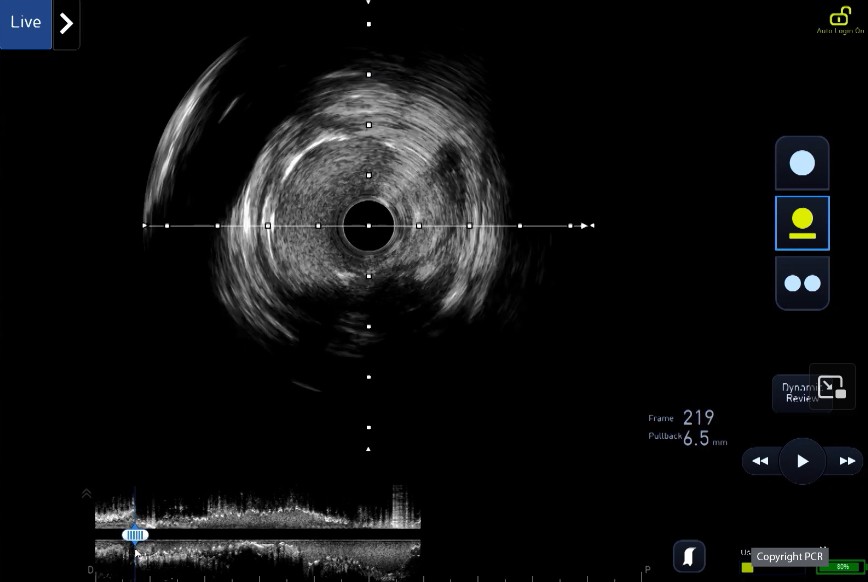

LIVE Educational Case: Provisional left main stenting after lesion preparartion guided by IVUS

Learn from replay📺pcronline.com/Cases-resource…

Operators: @DrShereen_ @FBardooli

Procedural Analyst: @GoranEBC

Key moments

🟣33:05–43:28 : Lesion preparation - IVL

🟣51:20–54:28 : Left main - LAD stenting

🟣24:00–31:20, 43:42–50:40, 58:20–1:01:50, 1:10:27–1:17:20 : IVUS at each step

This case has been editorialised by @MartineGilard